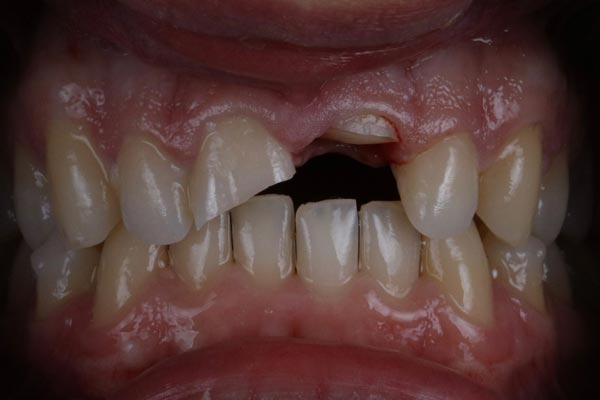

Traumatología dental

Ante un traumatismo dental, es fundamental realizar una valoración completa para determinar el alcance de la lesión.

En muchos casos, el CBCT resulta de gran utilidad para detectar posibles fracturas dentales y/o óseas que no siempre son visibles en las radiografías convencionales.

Además, se realizan pruebas de sensibilidad pulpar para evaluar el estado del nervio y comprobar si el diente mantiene su vitalidad o si requiere tratamiento endodóntico. Un diagnóstico preciso tras un trauma es clave para establecer el tratamiento adecuado y mejorar el pronóstico del diente a largo plazo.

Imágenes: Imagen de CBCT que muestra una fractura ósea de un paciente tras haber sufrido un trauma dental.

Imagen clínica de una fractura de corona de incisivos centrales después de un trauma.